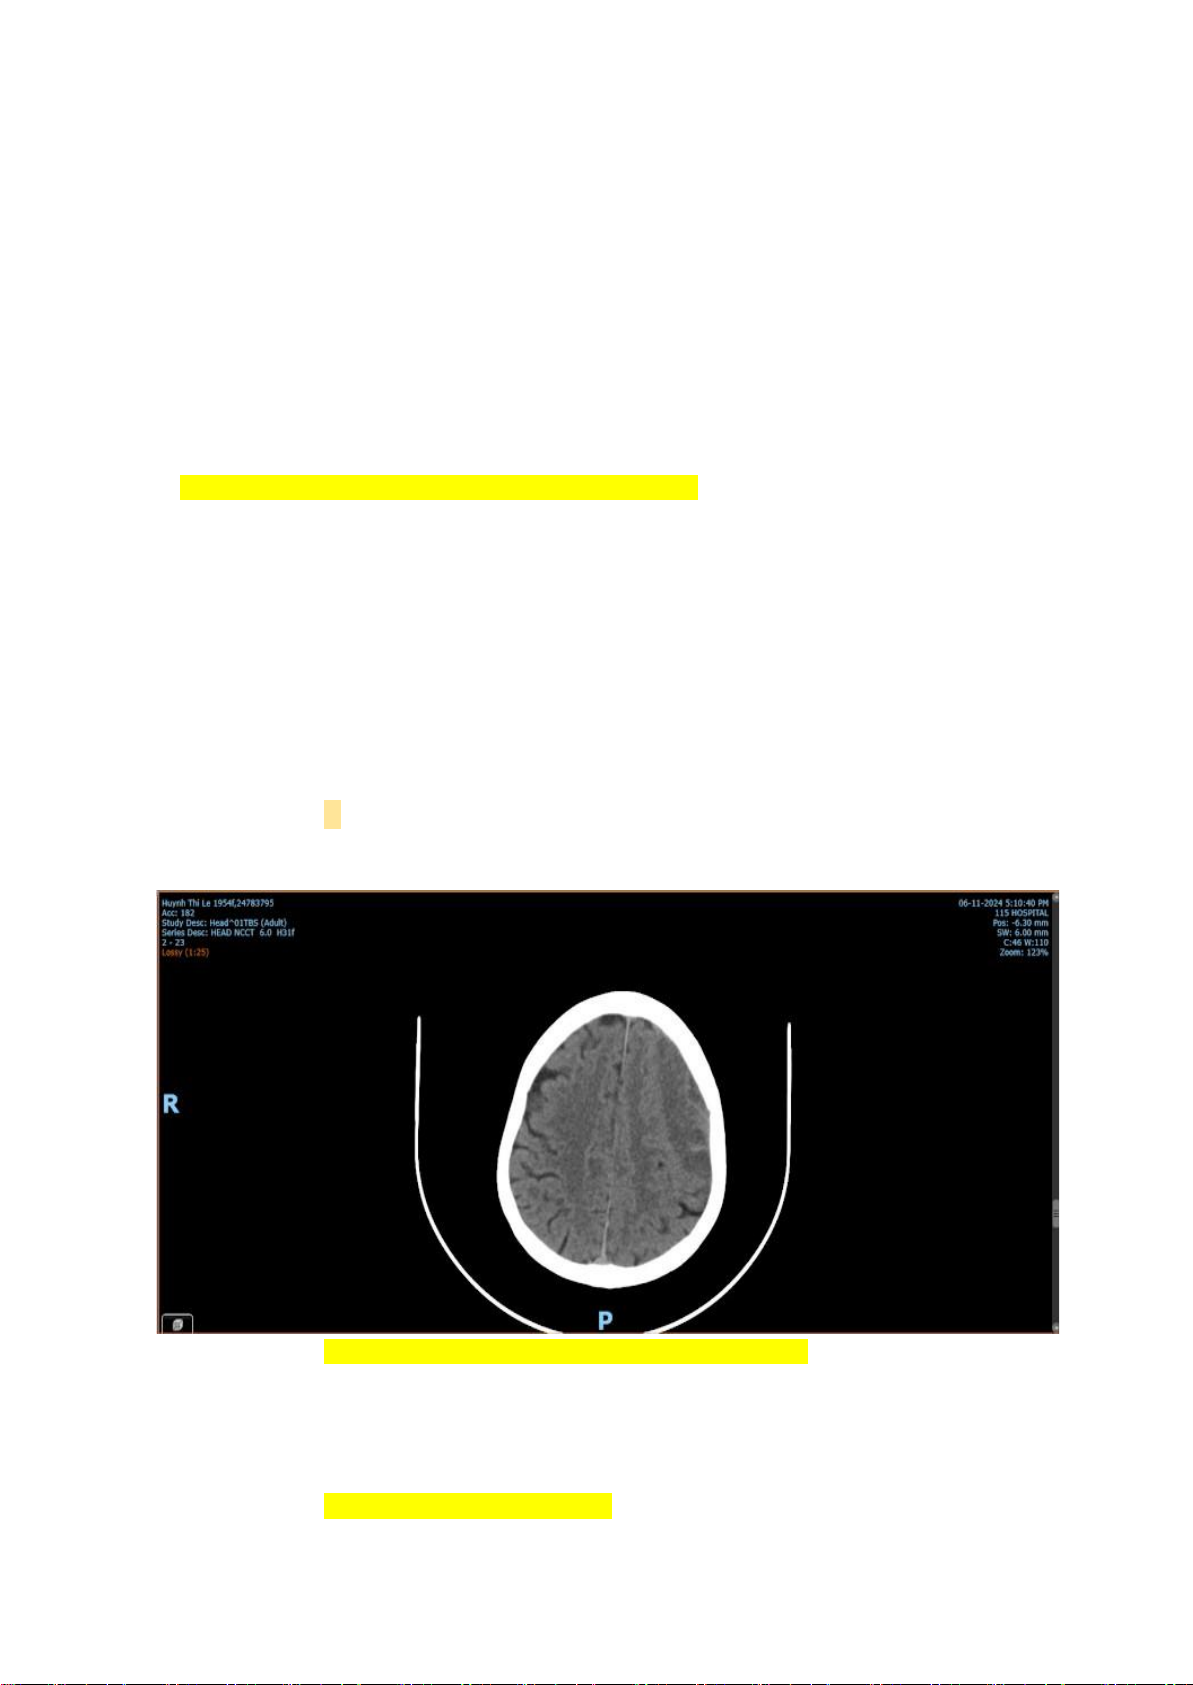

5. Phim CT của BN trên. Chẩn đoán

Máu tụ dưới màng cứng mạn tính bán cầu (T)

Máu tụ ngoài màng cứng mạn tính bán cầu (T)

Máu tụ ngoài màng cứng/ dưới màng cứng

Tụ máu dưới màng cứng 6. Xử trí của BN trên